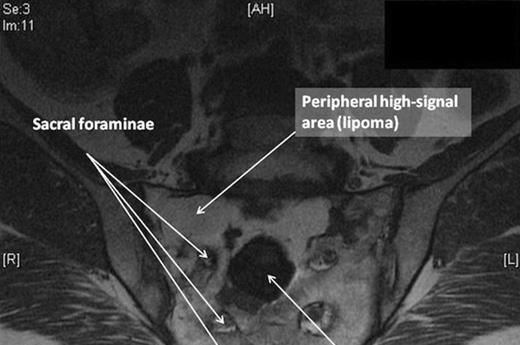

Blood tests including full blood count, urea & electrolytes and inflammatory markers were normal. The patient underwent plain radiographs, MRI and CT scans of the lumbar spine and pelvis. Plain radiographs of the spine and pelvis were normal. The MRI scan (fig. 1) revealed a heterogeneous mass within the proximal sacrum (high signal on T2-weighting), occupying the midline and extending to the sacral ala on the right side, measuring approximately 5x6 cm. Within this lesion was a 3cm area of abnormal low signal towards the midline of the sacrum. The lesion was in close proximity to the exiting right S1 and S2 nerve roots. The CT scan of the pelvis (fig. 2) confirmed the presence of a lytic lesion in the sacrum containing a smaller focus of different signal intensity.

This 58 year old female presented with acute-on-chronic low back pain with features of neurological compromise. Our patient’s presentation of diffuse low back pain with radiation to the lower limb is typical of degenerate disc disease but could also be seen in a sacral GCT. MRI revealed a mass within the sacrum consisting of two distinct parts: a peripheral high-signal area and a central low-signal area. The high intensity signal (on T2-weighting) was characteristic of fatty tissue. Radiographically, the central area was in keeping with a giant cell tumour (GCT), although typically these tend to occur eccentrically rather than in the midline. GCTs are low signal intensity on T1 and T2-weighted images, relating to the haemorrhagic and fibrotic components of the tumour (1). Histology revealed multinucleated cells, characteristic of the giant cells (resembling osteoclasts) that are pathognomic of GCT.